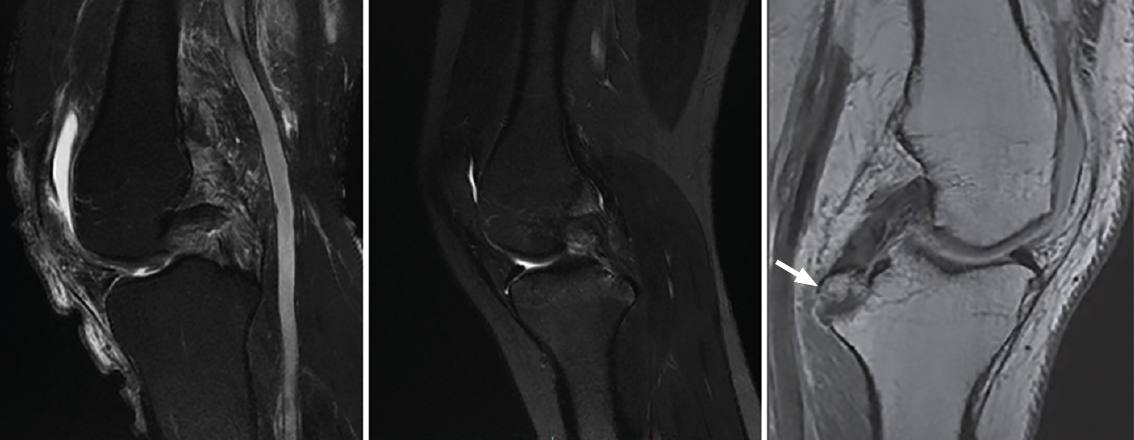

El patrón de lesión del LCP se divide en 3 tipos según su imagen en RM: lesión parcial o intrasustancia (Figura 6A), lesión completa (Figura 6B) y fractura avulsión a nivel de la inserción tibial (Figura 6C)(13,14). La mayoría de las lesiones completas se producen en la porción media del ligamento, que no se llega a visualizar correctamente en los planos axial y coronal, por lo que el gold standard es la evaluación de las imágenes en cortes sagitales(13,14).

reaca.28373.fs2101003-figura6.png

Figura 6. A: corte sagital de resonancia magnética (RM) en secuencia T2 donde se observa una rotura parcial; B: rotura total del ligamento cruzado posterior (LCP); C: corte sagital de RM en T1 de la rodilla izquierda. La flecha blanca indica la avulsión del LCP con fragmento óseo en la inserción tibial.